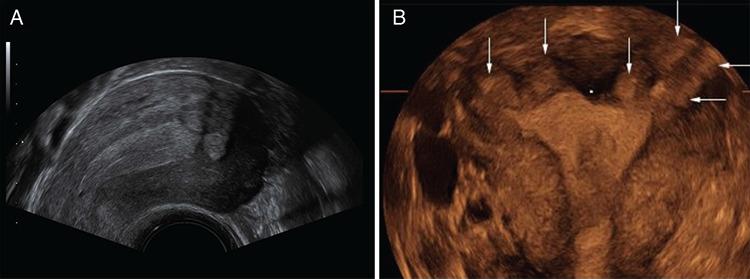

Endometriosis is one of the most common benign diseases in women of reproductive age. Nearly all gynecological offices and clinics will contain patients with endometriosis; the frequency and severity of the disease will vary from one setting to another. Adjoining specialties, such as internal medicine, general medicine, surgery, urology, orthopedics, neurology and psychosomatic medicine, will be challenged directly or indirectly by various forms of endometriosis and its sequelae. The disease is characterized by pelvic pain, dysmenorrhea, dyspareunia and sterility. Even now, several years may elapse between the onset of the disease and its diagnosis. The diagnosis of endometriosis is complicated by the diversity of the symptoms. A precise documentation of the patient’s medical history and thorough diagnostic procedures are essential to establish a robust diagnosis. This article will discuss the perioperative considerations, diagnosis and treatment of endometriosis.